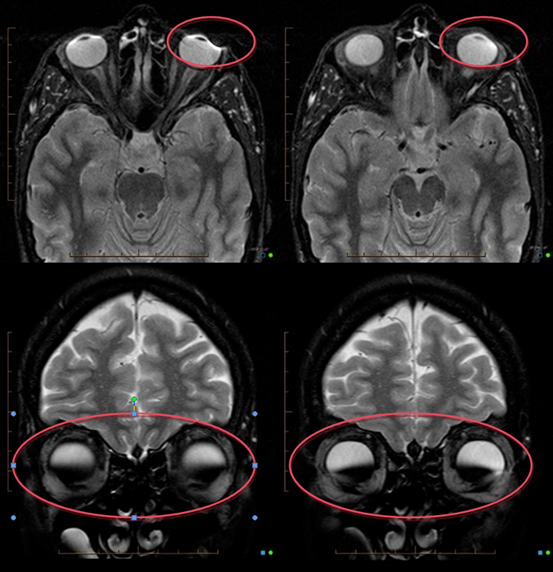

(未经纹眉患者的MRI影像)

(纹眉患者的MRI影像)

一名25岁的女性因为慢性炎症性神经系统疾病而需要接受颅脑MRI检查。这名患者的双眼上眼睑有美容性的纹身,也就是永久眼妆。在接受颅脑MRI检查过程中,该患者称她的上眼睑有烧灼感,于是检查立即终止。临床检查后发现:该患者的双侧上眼睑都出现了红斑,在患者被转回病房后又出现了上眼睑的水肿,被诊断为一度烧伤。